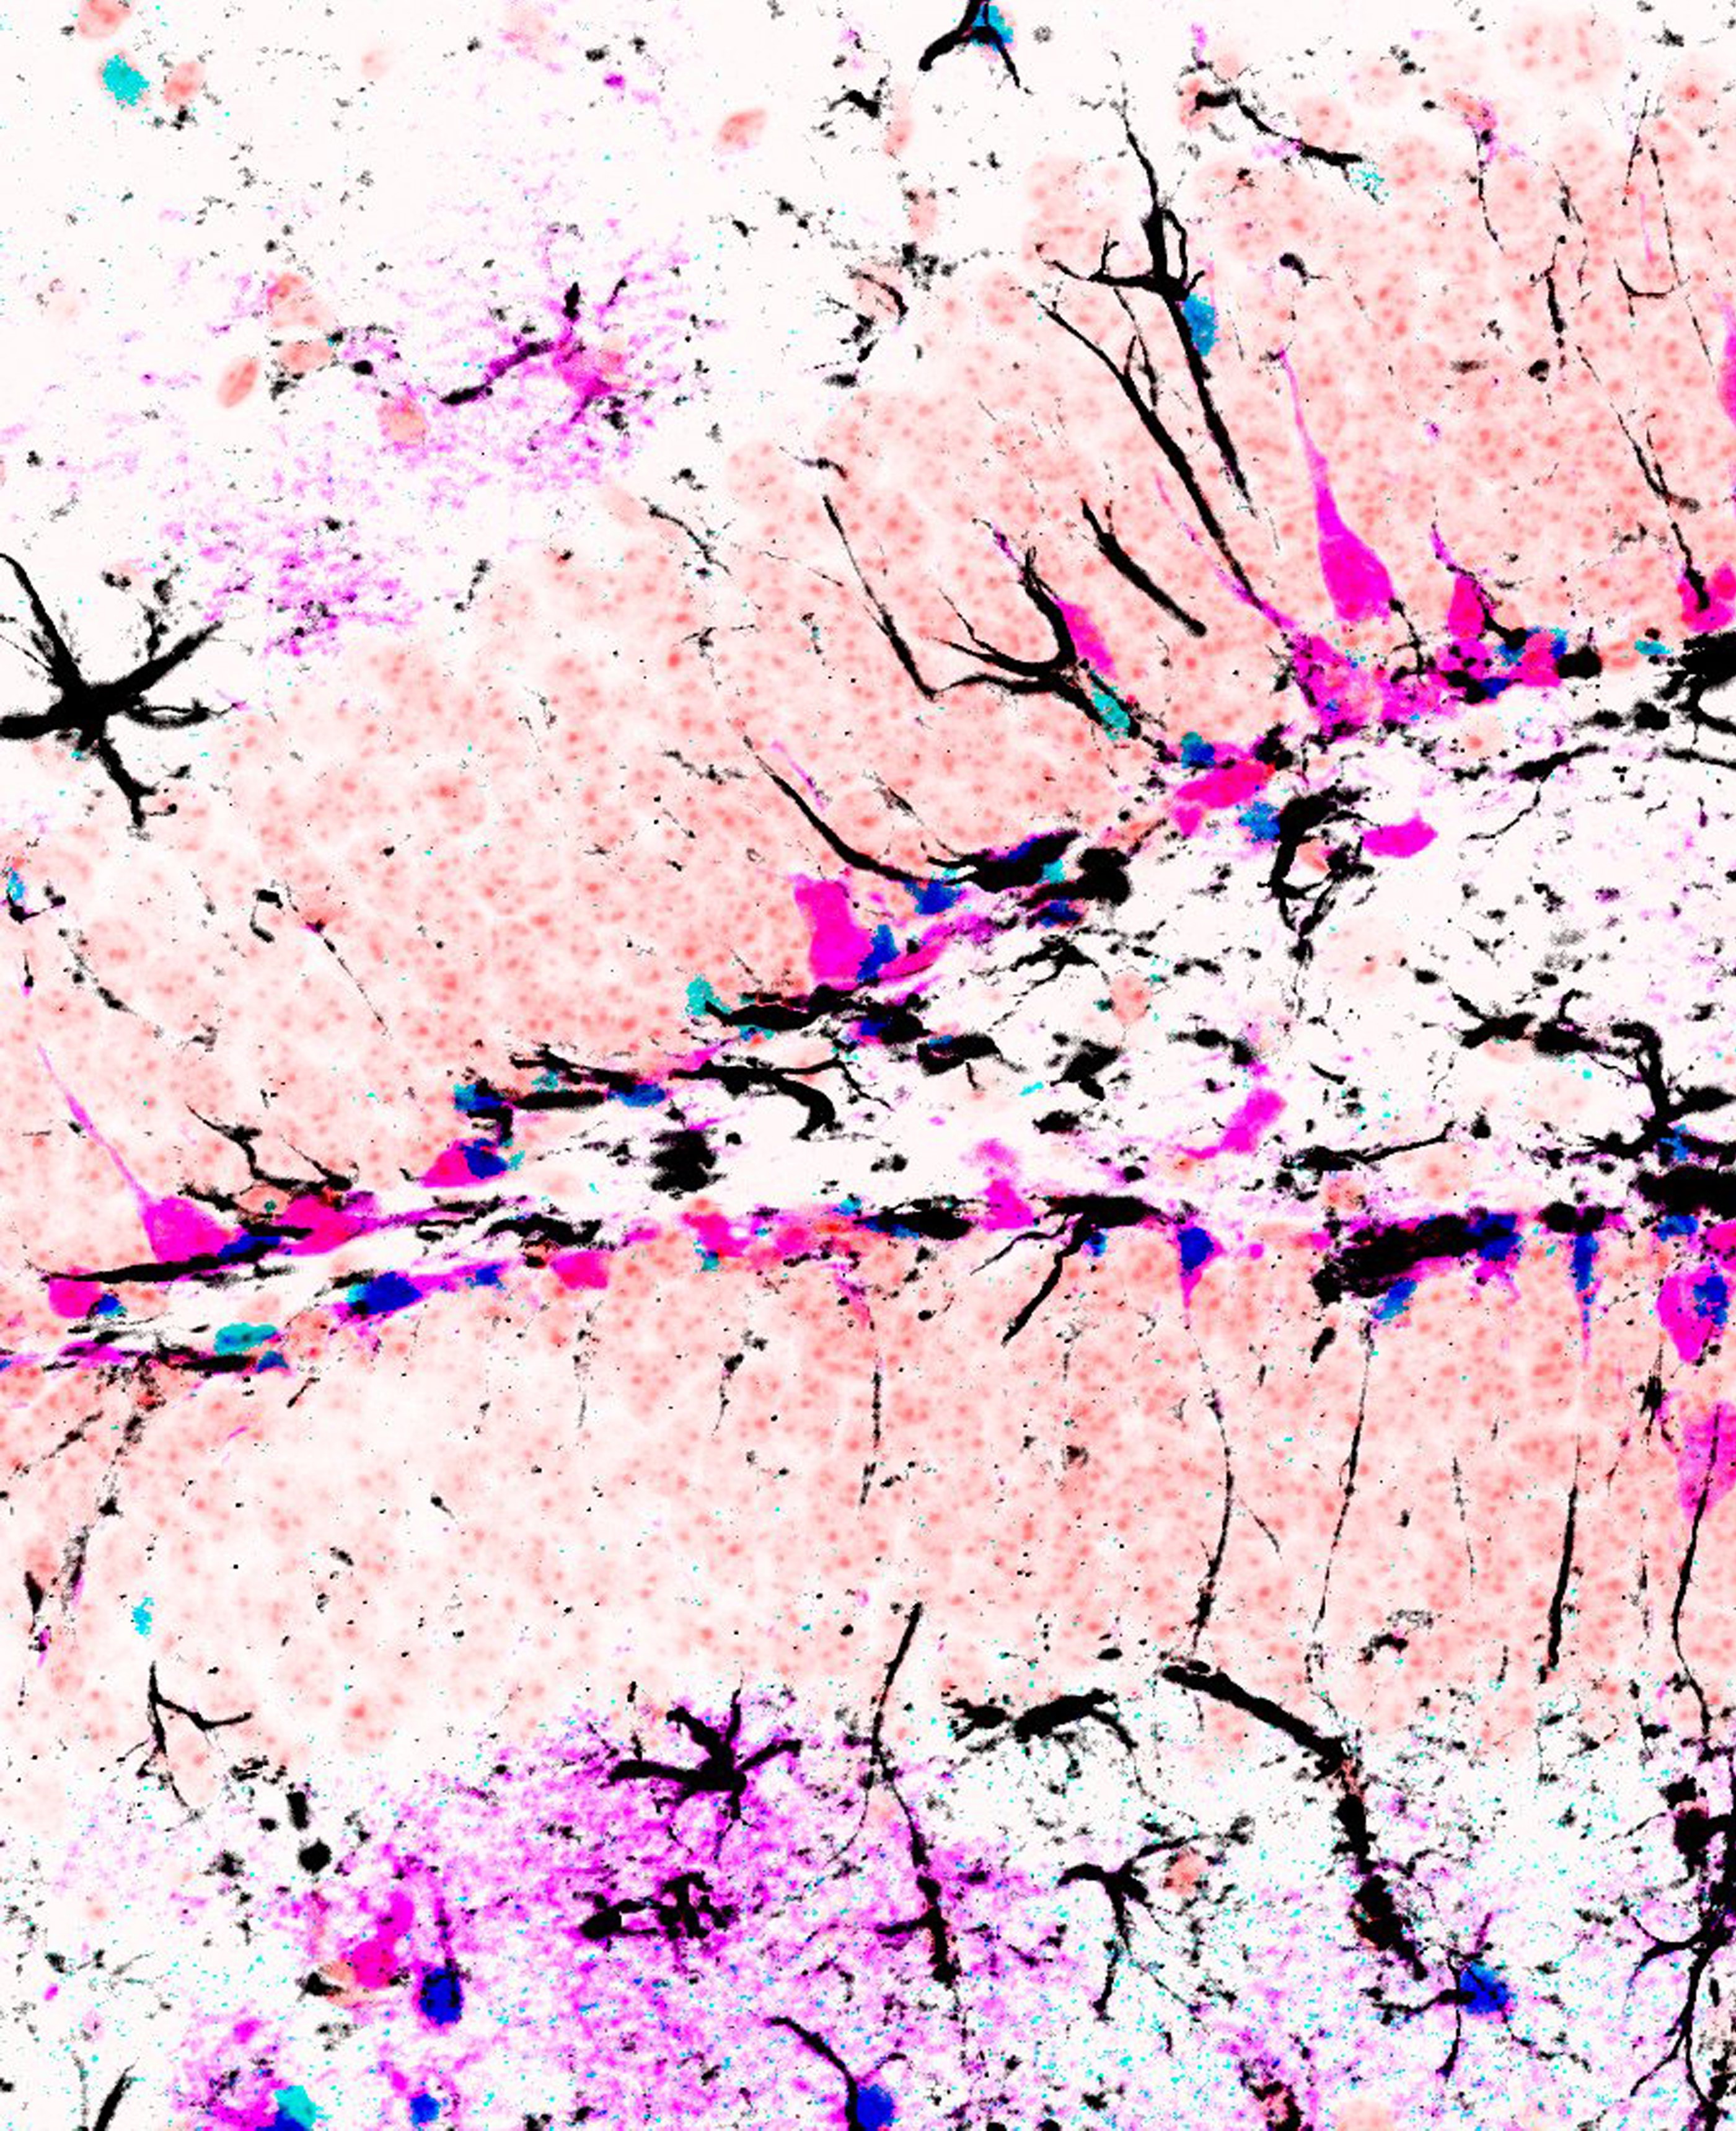

The study shows that the Notch2 signaling pathway controls the expression of a specific transcription regulator called Id4. Once expressed, Id4 inhibits the division of stem cells and blocks the production of new neurons in the hippocampus of the adult brain. Notch2 signaling maintains high levels of Id4 in some neural stem cells, and thereby explains why these stem cells increasingly enter a state of rest in the adult and geriatric brain.

As the brain ages, the Notch2-Id4 pathway enters into a state of hyperactivity, presenting a strong molecular brake that inhibits stem cell activation and neuron production. Conversely, inactivation of this pathway releases the brake and enables the production of new neurons - even in the brain of geriatric mice.

The results show that the stem cells in the mammalian brain are in a reversible resting state regulated by signals and factors in the niche. By manipulating the signaling pathway, the production of new nerve cells can be specifically stimulated.